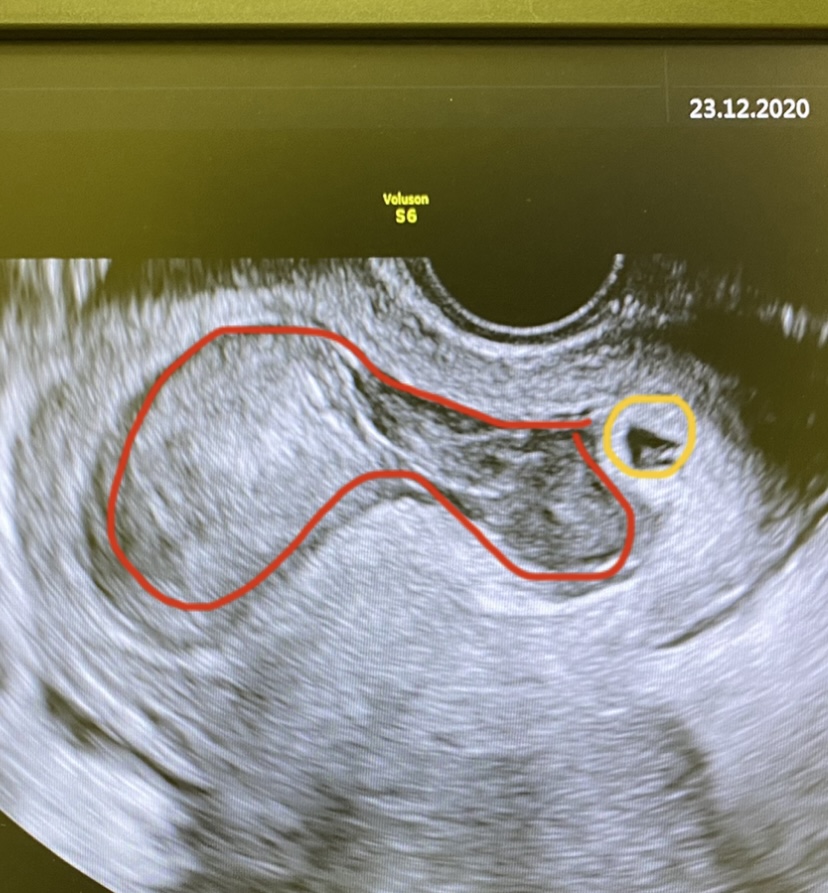

@emn88 ja neviem koľko má cm, ale že je 2/3tiny ako gestačný .. nešpiním vobec od vtedy jak som zakrvácala .. tak neviem :( .. uvidíme .. snáď to dopadne dobre, budem sa snažiť čo najviac ležať .. kontrolu mám až o 2 týždne .. lieky naďalej brat ako berem

@nikadominikanika ja som sa ta preto pytala ze ci nemas foto, ja som takto mala pred par rokmi, zlte bolo embryjko vo vaku a to cele bol hematom, a to vswtci hned ze masivny hematom, ze bez sance, aj k odbornikom ma hned posielali..tak verim ze u teba to nema az taketo giganticke rozmery a vstrebe sa🙏🏼 aj ascorutin je fajn brat mne vtedy odporucali a pit citronovu vodu